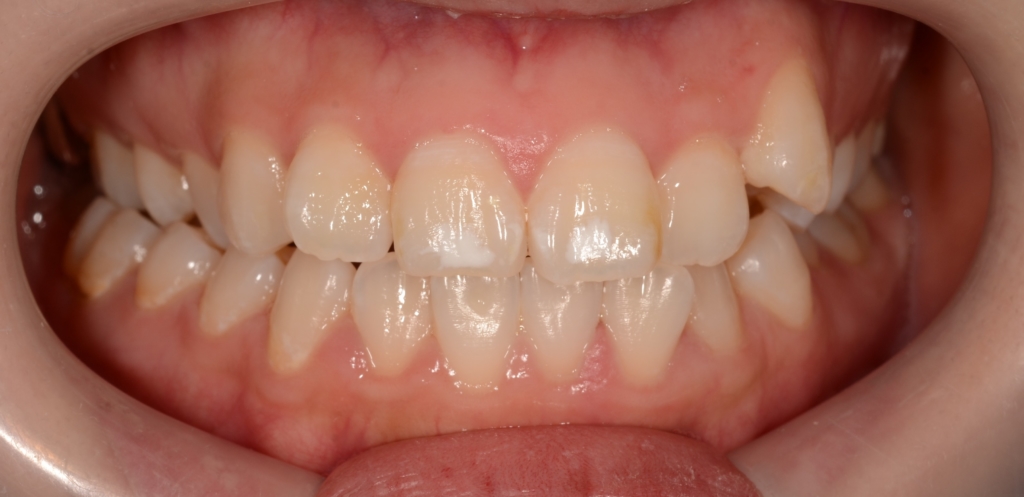

【Before】

#1.上下顎前突

#2.歯と顎の不調和による叢生(軽度)

と診断しました。